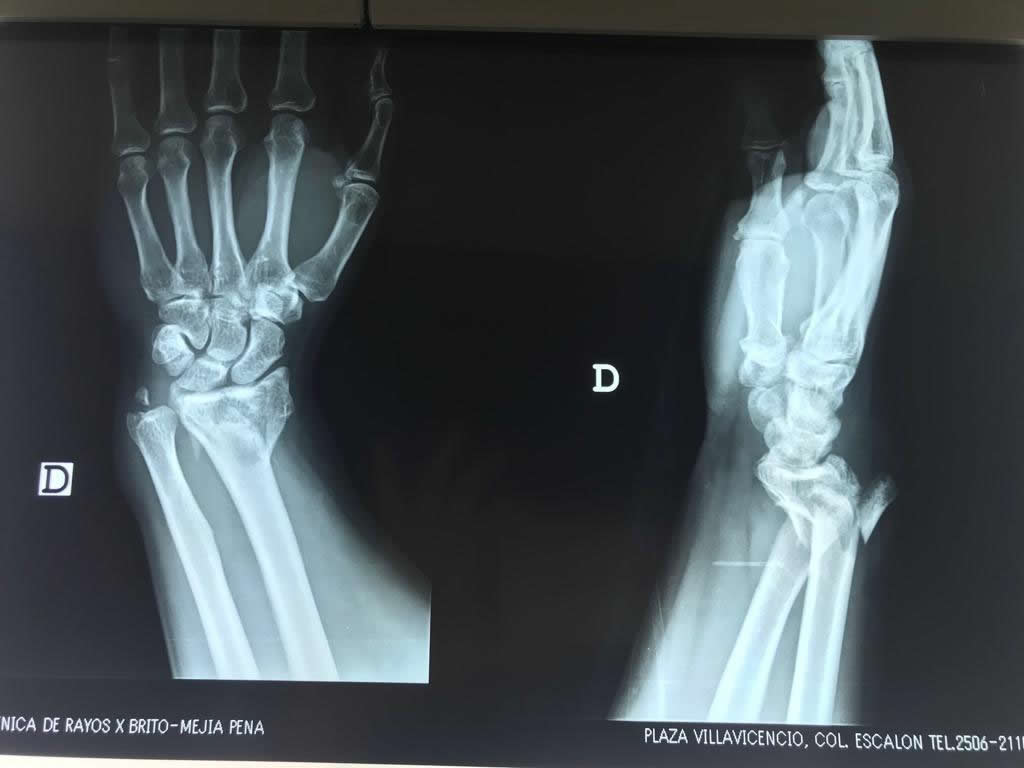

Cirugías de Muñecas

Los procedimientos más comunes en cirugía de la mano son aquellos destinados a reparar traumatismos, incluyendo lesiones de tendones, nervios, vasos sanguíneos, y articulaciones; huesos fracturados; y quemaduras, cortes, y otros daños de la piel.